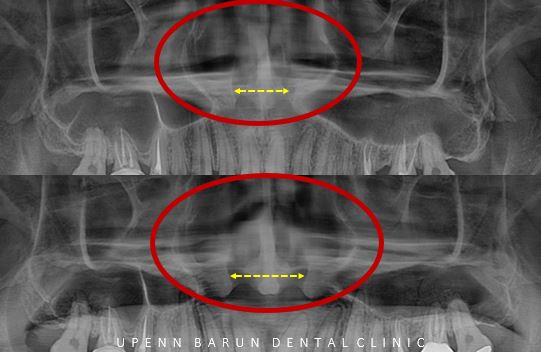

Case 4

마지막으로 소개해 드릴 환자분께서는

턱이 삐뚤어졌고 ,평소 코로 숨을 쉬는게 불편해서

대학병원을 방문했지만 성장판이 닫혔다며 양악수술을 권유받으셨다고 해요.

하지만 환자분은 수술대신 교정과 확장장치를 통해

비수술적으로 최대한 개선하고 싶어 저희병원을 찾아주셨는데요.

치료기간 23.5 ~ 23.6

사실 악궁확장장치는

코 안쪽의 공간을 (=비강)을 넓혀주어

단기적으로 코로 숨을 쉴때

더욱 효과적으로 호흡을 도와줍니다.

실제로

악궁확장장치 후 코가 좀 더 뚫린 느낌을 받으시고

이전과 달리

숨쉬기가 더 편해졌다고 합니다^^

환자분들의 만족도가 높은 교정장치중의 하나입니다.